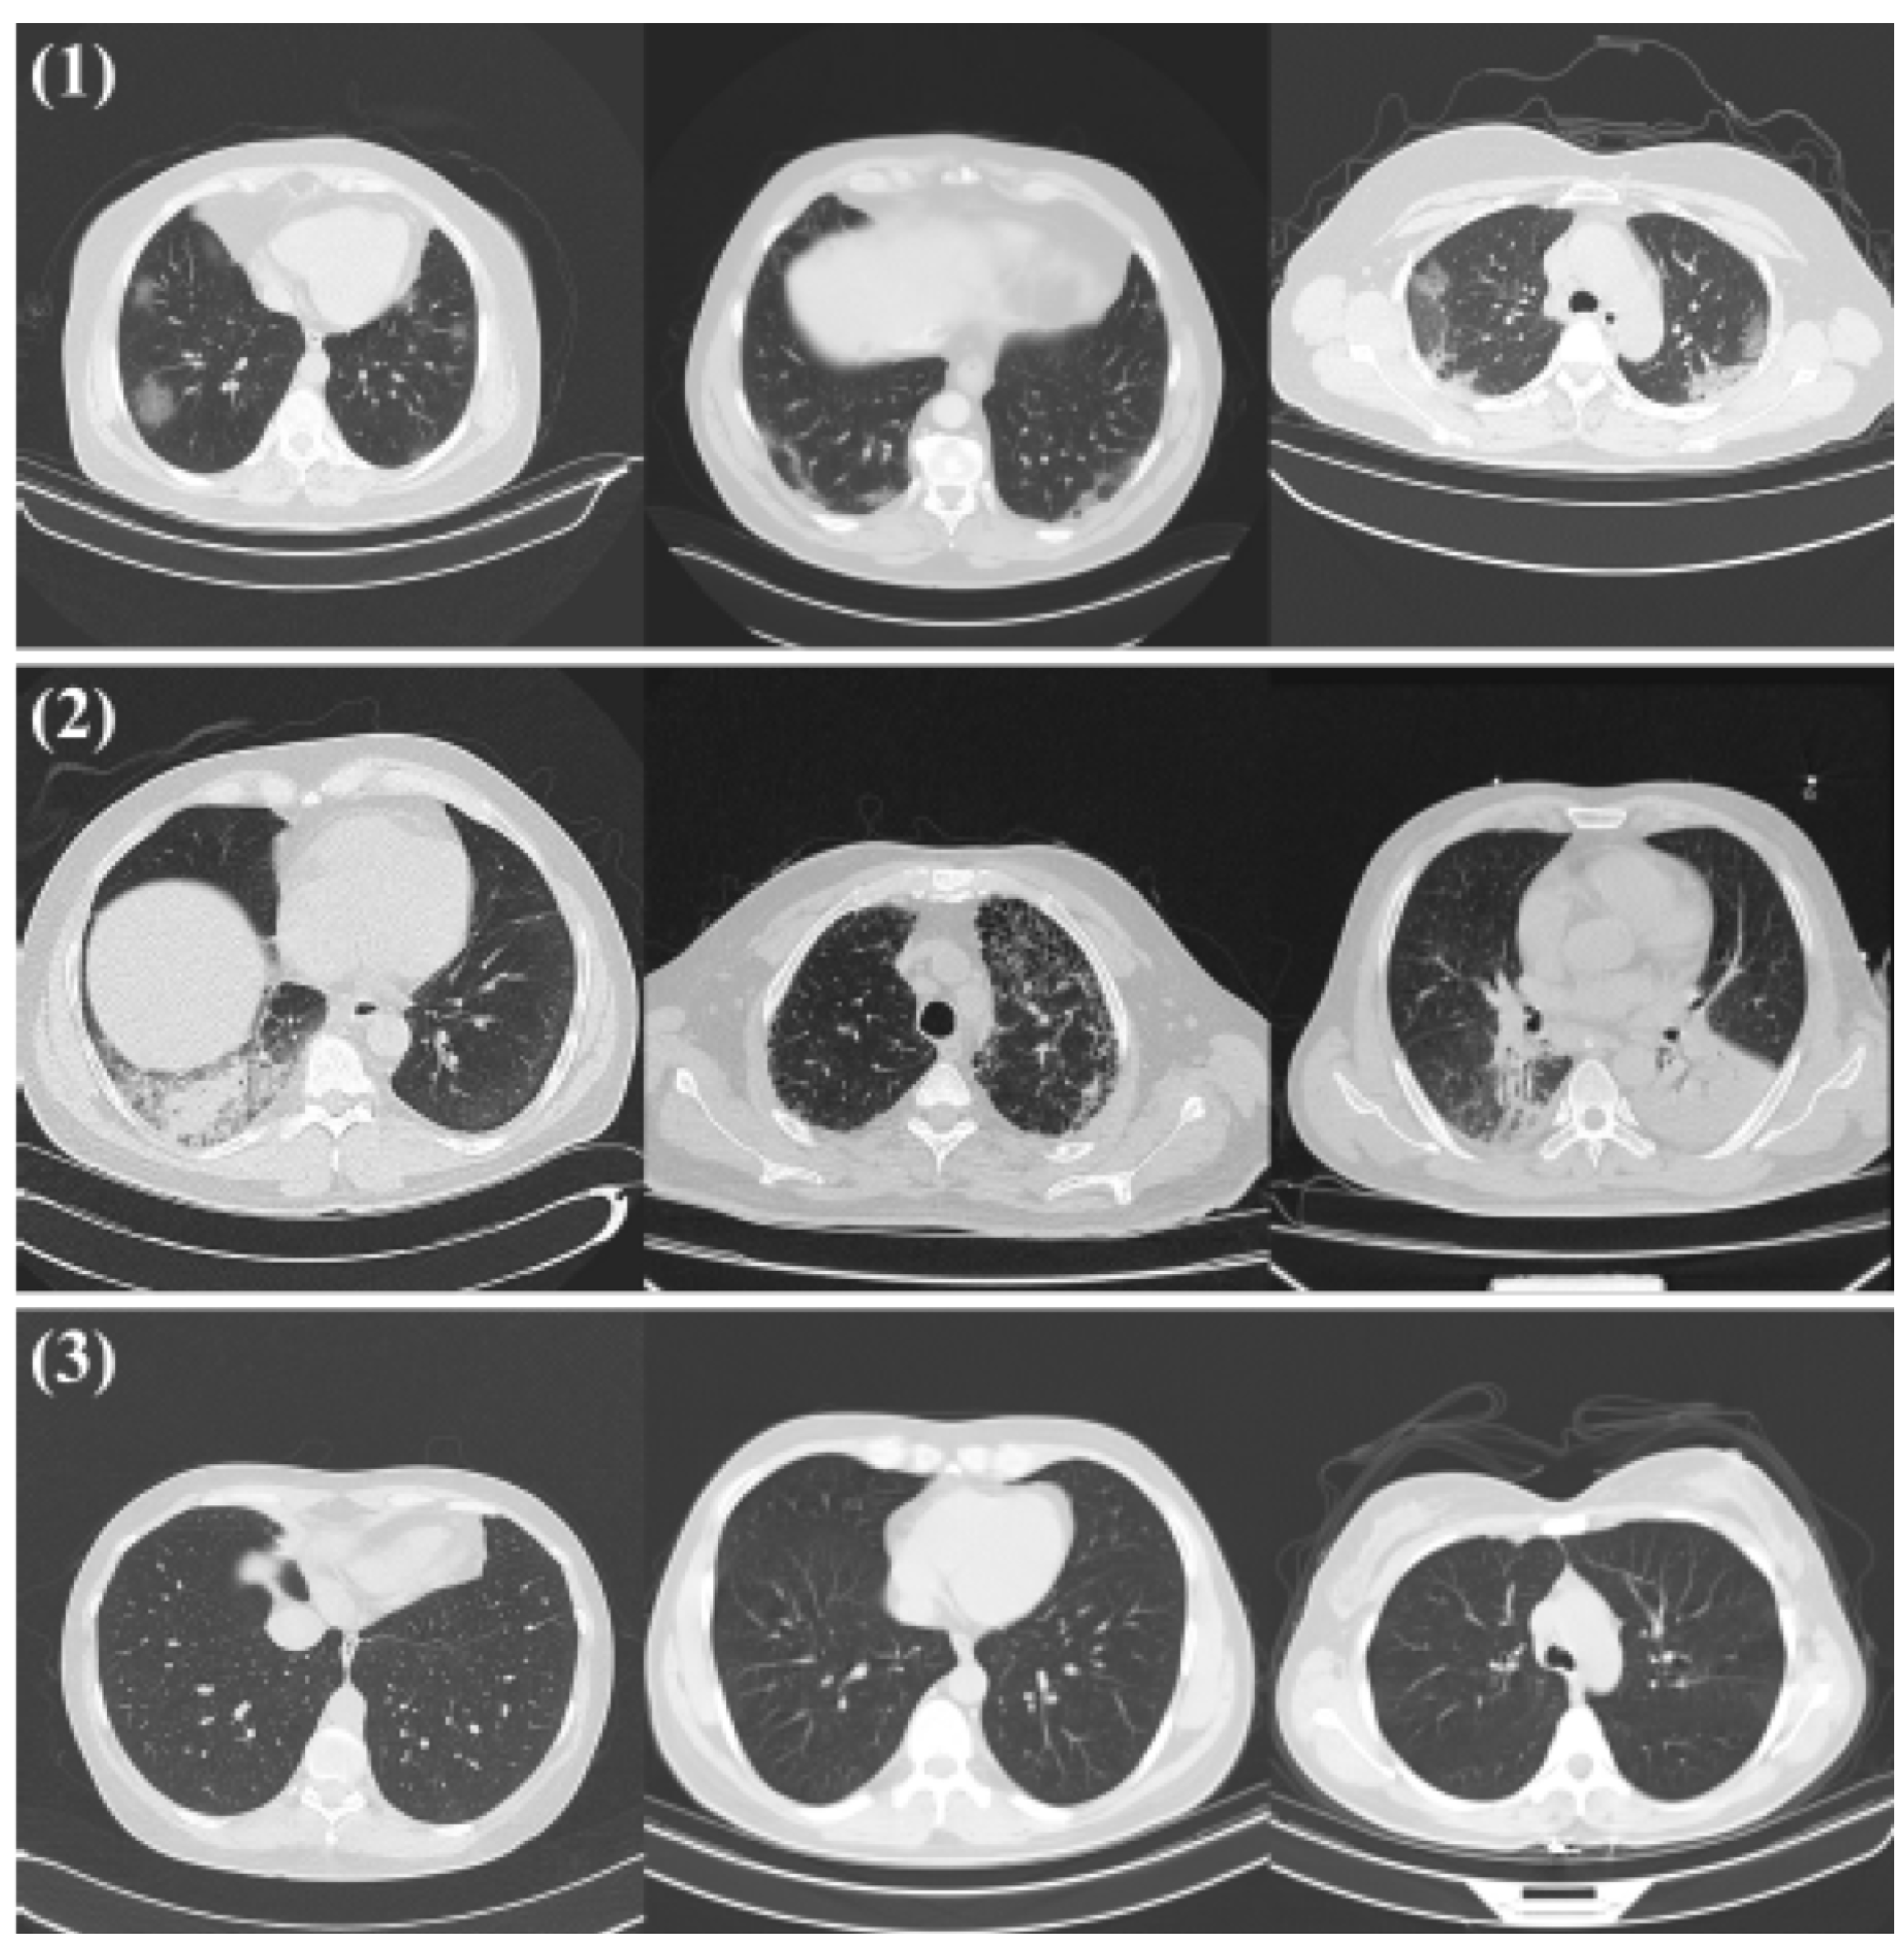

2.1.2. COVID-CT Dataset